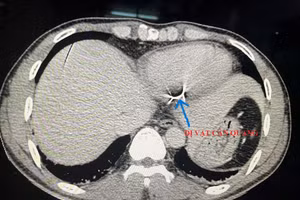

Đi cắt cỏ, người đàn ông bị mảnh lưỡi máy cắt đâm vào tim 05/05/2022 12:47 GD&TĐ - Người đàn ông 35 tuổi trong lúc sử dụng máy cắt cỏ đã cắt phải dây kẽm gai khiến mảnh lưỡi máy cắt đâm xuyên bụng, sau đó đâm vào tim.